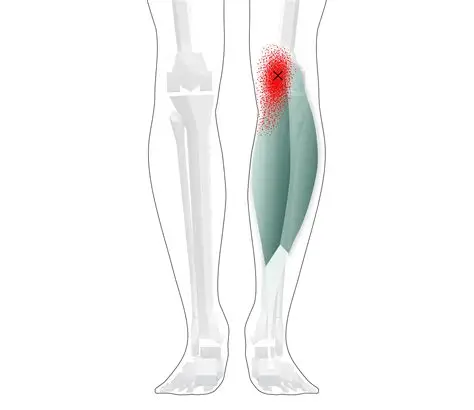

Gastrocnemius Rupture